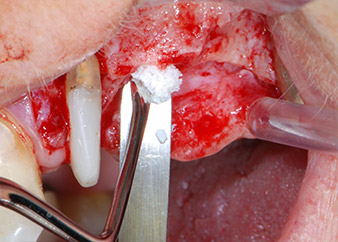

CPITN-сонда

Фиг. 10: Поставяне на ксеногенен костозаместващ материал в имплантологичната остеотомия за вътрешна синусна аугментация. Материалът е внимателно кондензиран в апикална посока със сферичната CPITN сонда (не е показано).

Преди поставянето на имплант, и последвалото потвърждение за непокътната Шнайдерова мембрана (Фиг. 9), вътрешният синус е повдигнат и в двете места на имплантите с помощта на ксеногенен костозаместващ материал (Bio-Oss, Geistlich Biomaterials) (Фиг. 10).